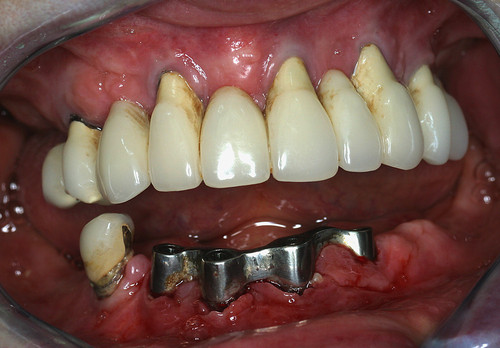

L’état initial (fig.26) montre une péri implantite généralisée au maxillaire et à la mandibule.

Fig. 26

Infection généralisée des implants dentaires